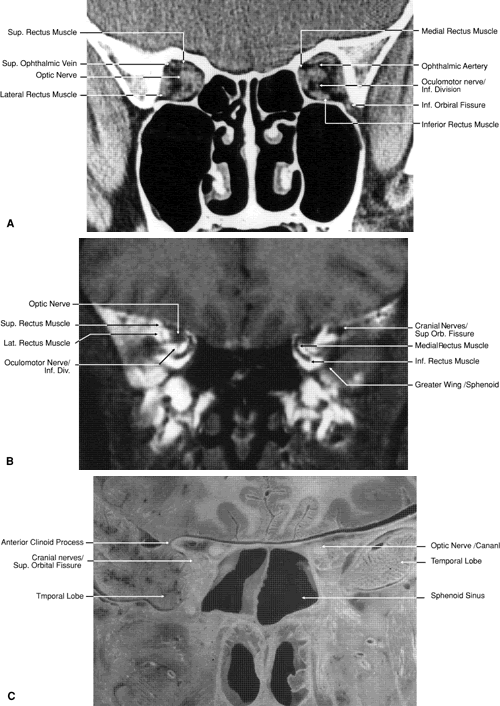

Fig. 20. Coronal images through orbital apex. A. Computed tomography scan. B. T1-weighted magnetic resonance imaging. C. Anatomic section of a cadaver head at the level of the orbital apex.

Fig. 21. Coronal images through optic canal. A. Computed tomography scan. B. T1-weighted magnetic resonance imaging.